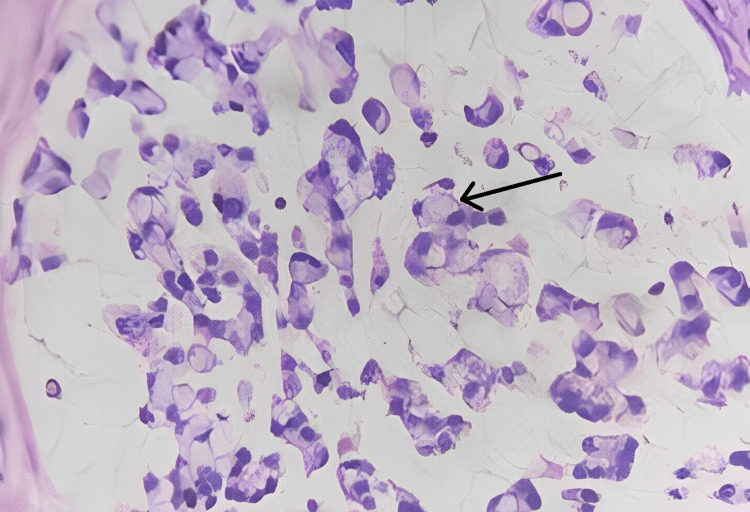

Microscopic findings

Sections studied from the ampullary growth revealed mucosa lined by columnar epithelium infiltrated by diffuse sheets of signet ring cells. These cells had vacuolated cytoplasm and hyperchromatic pleomorphic eccentric nuclei. Areas of mucin pools were seen. A dense inflammatory infiltrate was seen in lamina propria, submucosa, and muscularis propria. The serosa showed inflammatory cells and congested blood vessels. Sections studied from both proximal and distal margins were free from tumor invasion. Sections studied from the duodenum, gall bladder, pancreas, mesentery, and CBD were free from tumor invasion.

Signet ring cell adenocarcinoma of the ampulla of Vater (TisN0M0) Stage 0 (Figures 2–4).